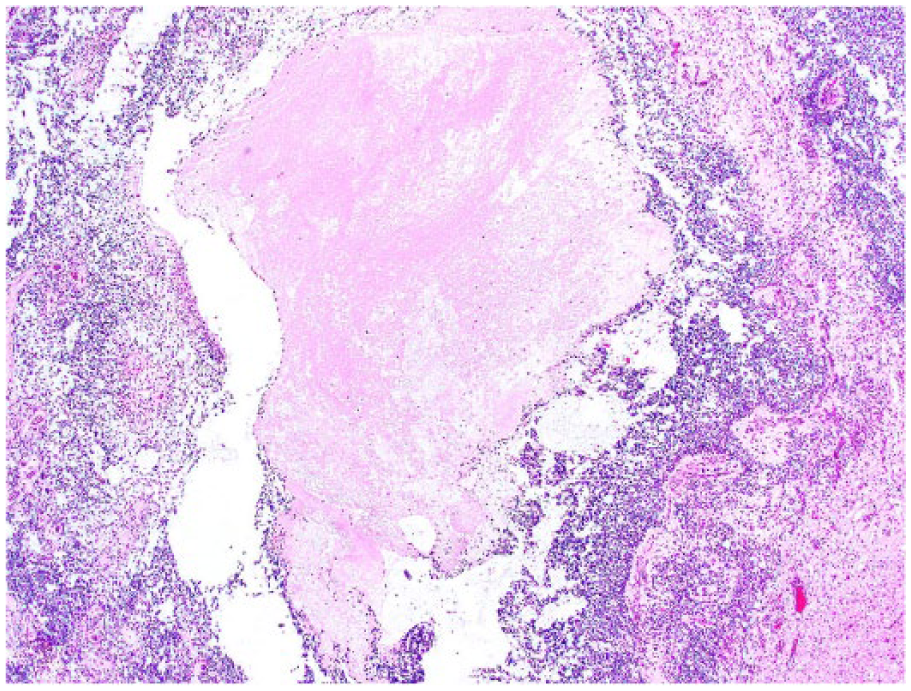

Histologically, all tumors were poorly demarcated, often infiltrative, and affected mainly the spinal gray matter. Oligodendrogliomas (cases 1, 3, 6, and 7) were poorly demarcated and affected primarily the gray matter, but also extended into the adjacent white matter (Fig. 2). Neoplastic cells were arranged in sheets or cords supported by preexisting parenchyma or a fine fibrovascular stroma with occasional microvascular clusters (glomeruloid vessels; cases 3 and 6). Neoplastic cells were mildly to moderately pleomorphic and had a moderate amount of cytoplasm, with distinct borders, that was either clear (forming a perinuclear halo) or contained basophilic, fibrillar, mucinous material. Nuclei were round-to-oval and had finely stippled to dense chromatin and 1–4 nucleoli. Overall mitotic activity was absent or low. Small areas of necrosis and hemorrhage were present in all 4 tumors. Case 6 was highly cellular and had increased cellular pleomorphism, with extensive areas of necrosis (Fig. 3) and 19 mitoses in ten 400× fields. Cases of gliomatosis cerebri (cases 4 and 5) were characterized by extensive, segmental, unilateral infiltration of neoplastic glial cells throughout the dorsal, lateral, and ventral funiculi and ventral horn of the spinal cord with no discrete mass formation (Fig. 4). There was a lack of distinction between the white and gray matter in the affected areas. Neoplastic cells were supported by preexisting neural tissue or small numbers of capillaries and had a moderate amount of round-to-polygonal, eosinophilic, vacuolated cytoplasm with indistinct borders. Nuclei were round-to-oval and had finely stippled chromatin with indistinct nucleoli. Mitotic index was 7 (case 4) and 11 (case 5) in ten 400× fields. Areas of hemorrhage or small perivascular accumulations of lymphocytes and plasma cells were observed occasionally. The astrocytoma (case 2) was poorly demarcated and affected both gray and white matter, although it appeared to arise primarily from the gray matter (Fig. 5). Neoplastic cells were widespread throughout the affected areas and were supported by preexisting neural tissue. These cells had moderate pleomorphism and scant, round-to-polygonal, eosinophilic cytoplasm with distinct borders. Nuclei were round to slightly elongate and had densely coarse chromatin with indistinct nucleoli. Mitoses were absent. IHC findings are summarized in Table 2 and shown in Figures 6–9. The main features of canine glial tumors of the spinal cord reported in the veterinary literature are summarized in Supplemental Table 1 (available at http://vdi.sagepub.com/content/by/supplemental-data).

Spinal anaplastic oligodendroglioma in dog 6. The tumor is highly cellular with extensive areas of necrosis (center). H&E.